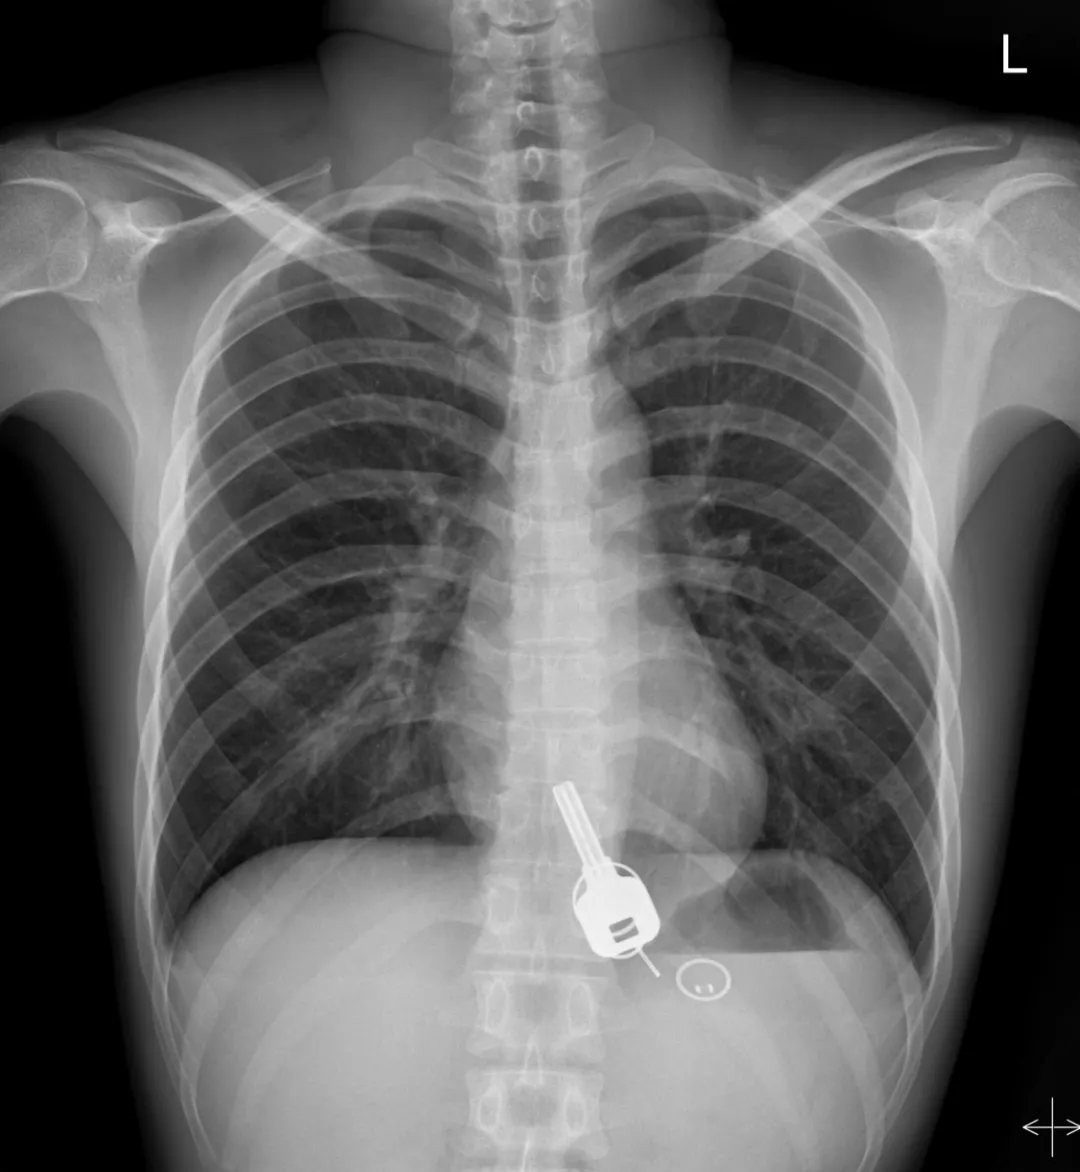

廣東東莞的常先生酒后回家找不到鑰匙,酒醒后他感到胸口疼痛,去醫(yī)院一查,發(fā)現一把鐵鑰匙、2個鑰匙扣、1個門禁牌清楚顯示在肚子胃區(qū)的位置上。

醫(yī)生準備在胃鏡下取出鑰匙,不料,因鑰匙太大在常先生喉嚨附近食管入口處卡住了,取不出來,最后,醫(yī)生決定給常先生做無痛胃鏡,麻醉后,常先生食管入口處肌肉松弛,鑰匙終于順利取出!。